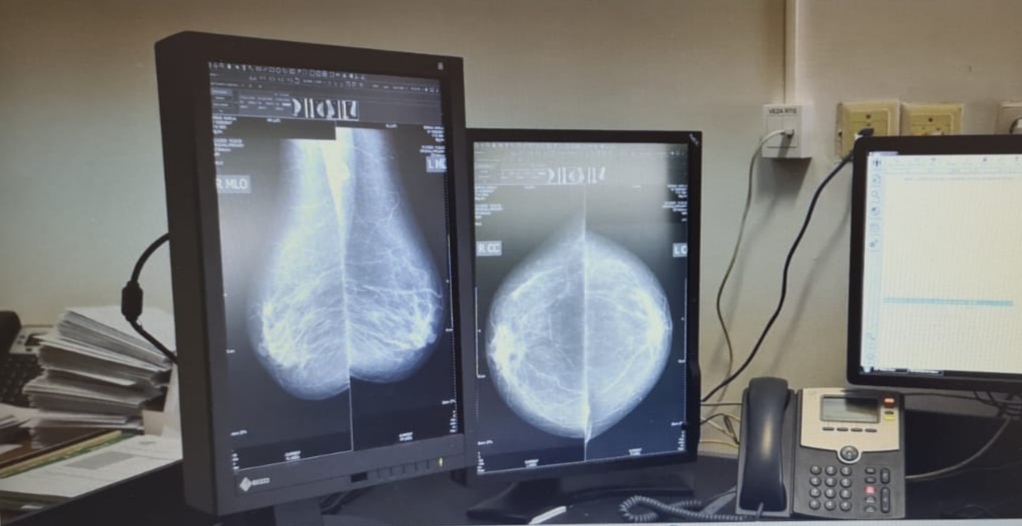

Uz sanitetsko vozilo nabavljen je softverski sustav koji će omogućiti povezivanje sustava RTG kabineta sa ordinacijama primarne i specijalističke zdravstvene zaštite. Cilj nabavke ovog softvera je integracija radiološke djelatnosti u jedan jedinstveni informacijski sustav koji će omogućiti pregled slika i radioloških nalaza nezavisno od mjesta gdje su slike nastale.